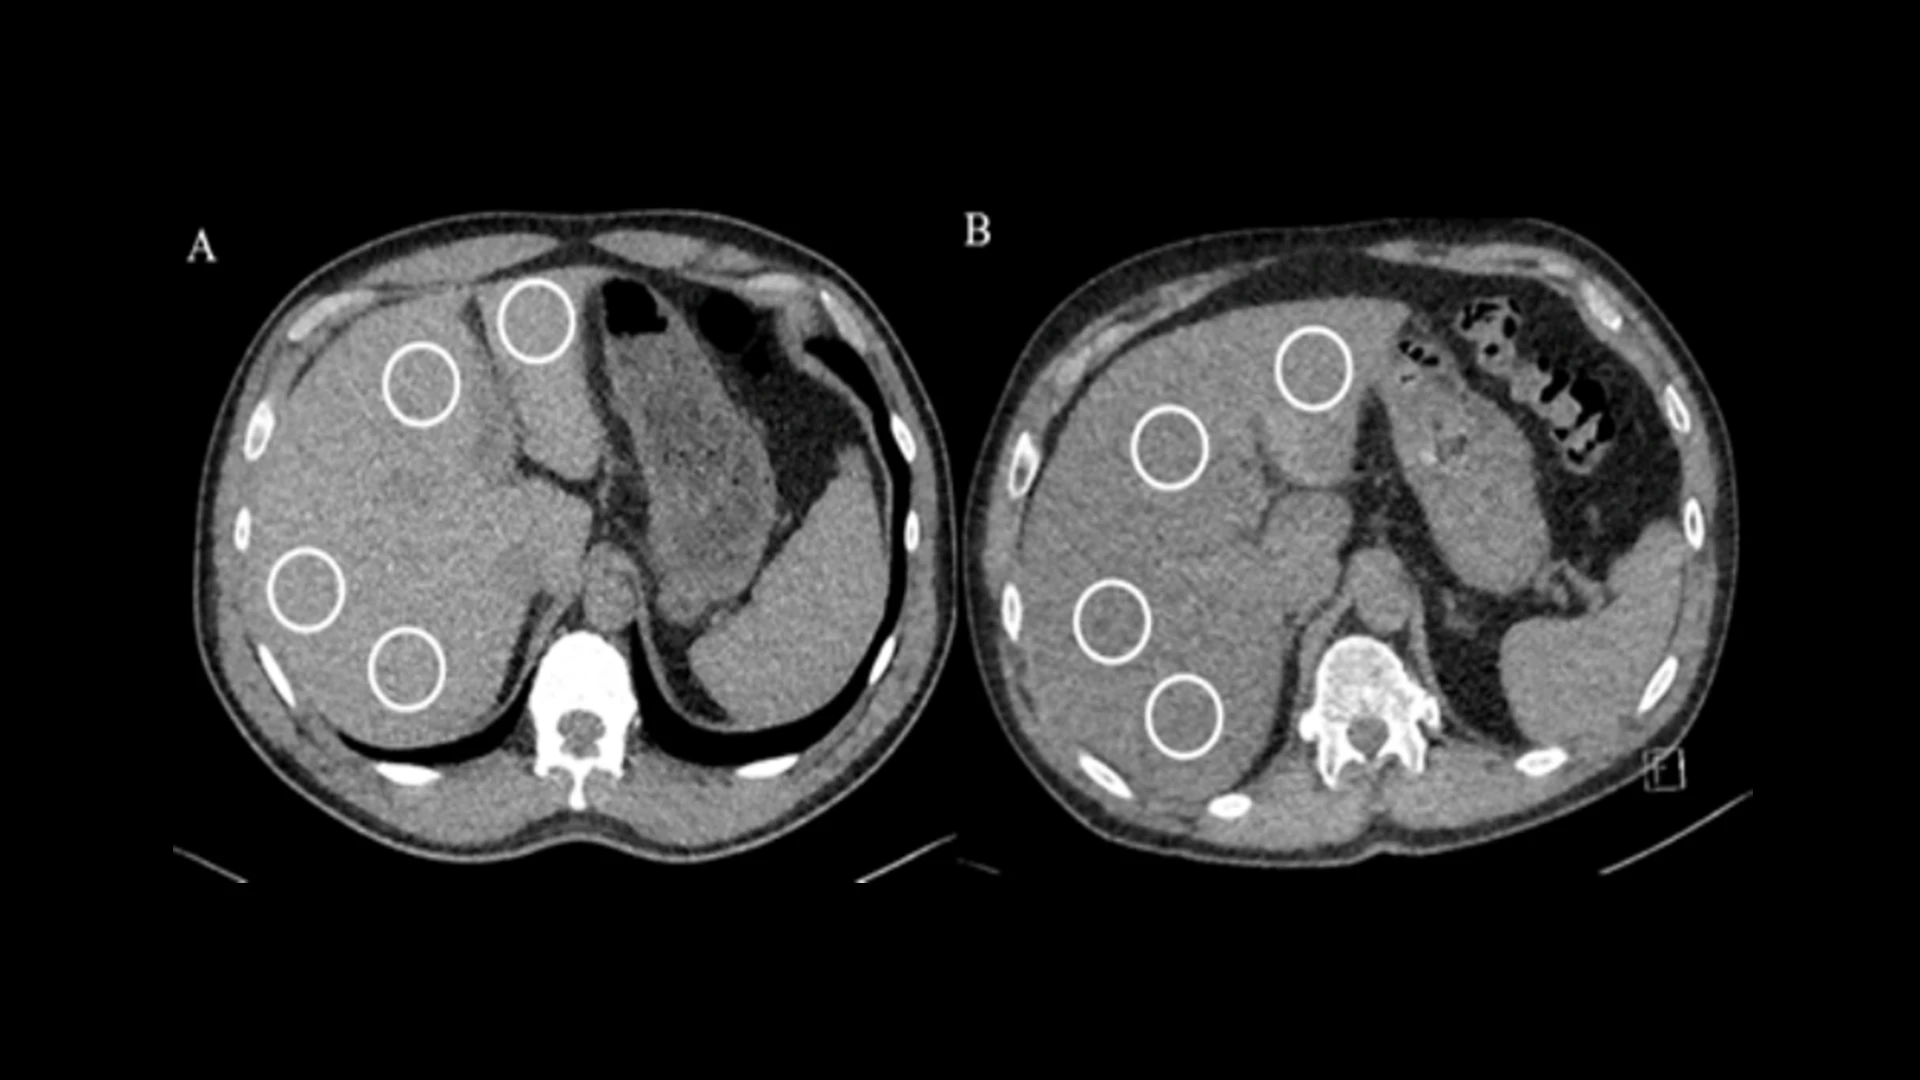

Liver density measurements on non-contrast chest CT in WTC participants. Averaged normal liver attenuation (59.5 HU) was noted in a 56-year-old male (A) and averaged lower liver attenuation (25 HU) was noted in a 57-year-old male (B), consistent with hepatic steatosis. Region of interest (white circles) measurements were placed in the right posterior, right anterior, left medial, and left lateral segments of the liver to determine liver attenuation, avoiding lesions and vessels.